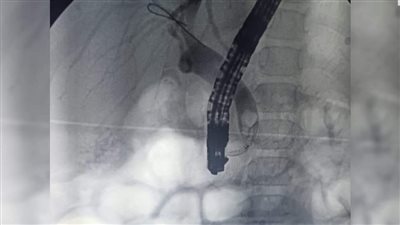

"انسداد المرارة".. تركيب دعامة بلاستيكية لطفلة 7 سنوات ضمن منظومة التأمين الصحي الشامل ببورسعيد